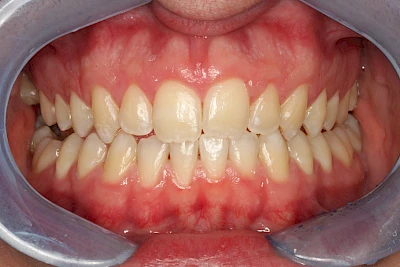

Verfärbungen an Zähnen können außen aufgelagert oder im Zahn eingelagert sein.

Von außen (exogen) eher dunkel gefärbt und meist mehrere Zähne betroffen:

- Genußmittel (Tee, Kaffee, Rauchen)

- Medikamente (z. B. Eisen)